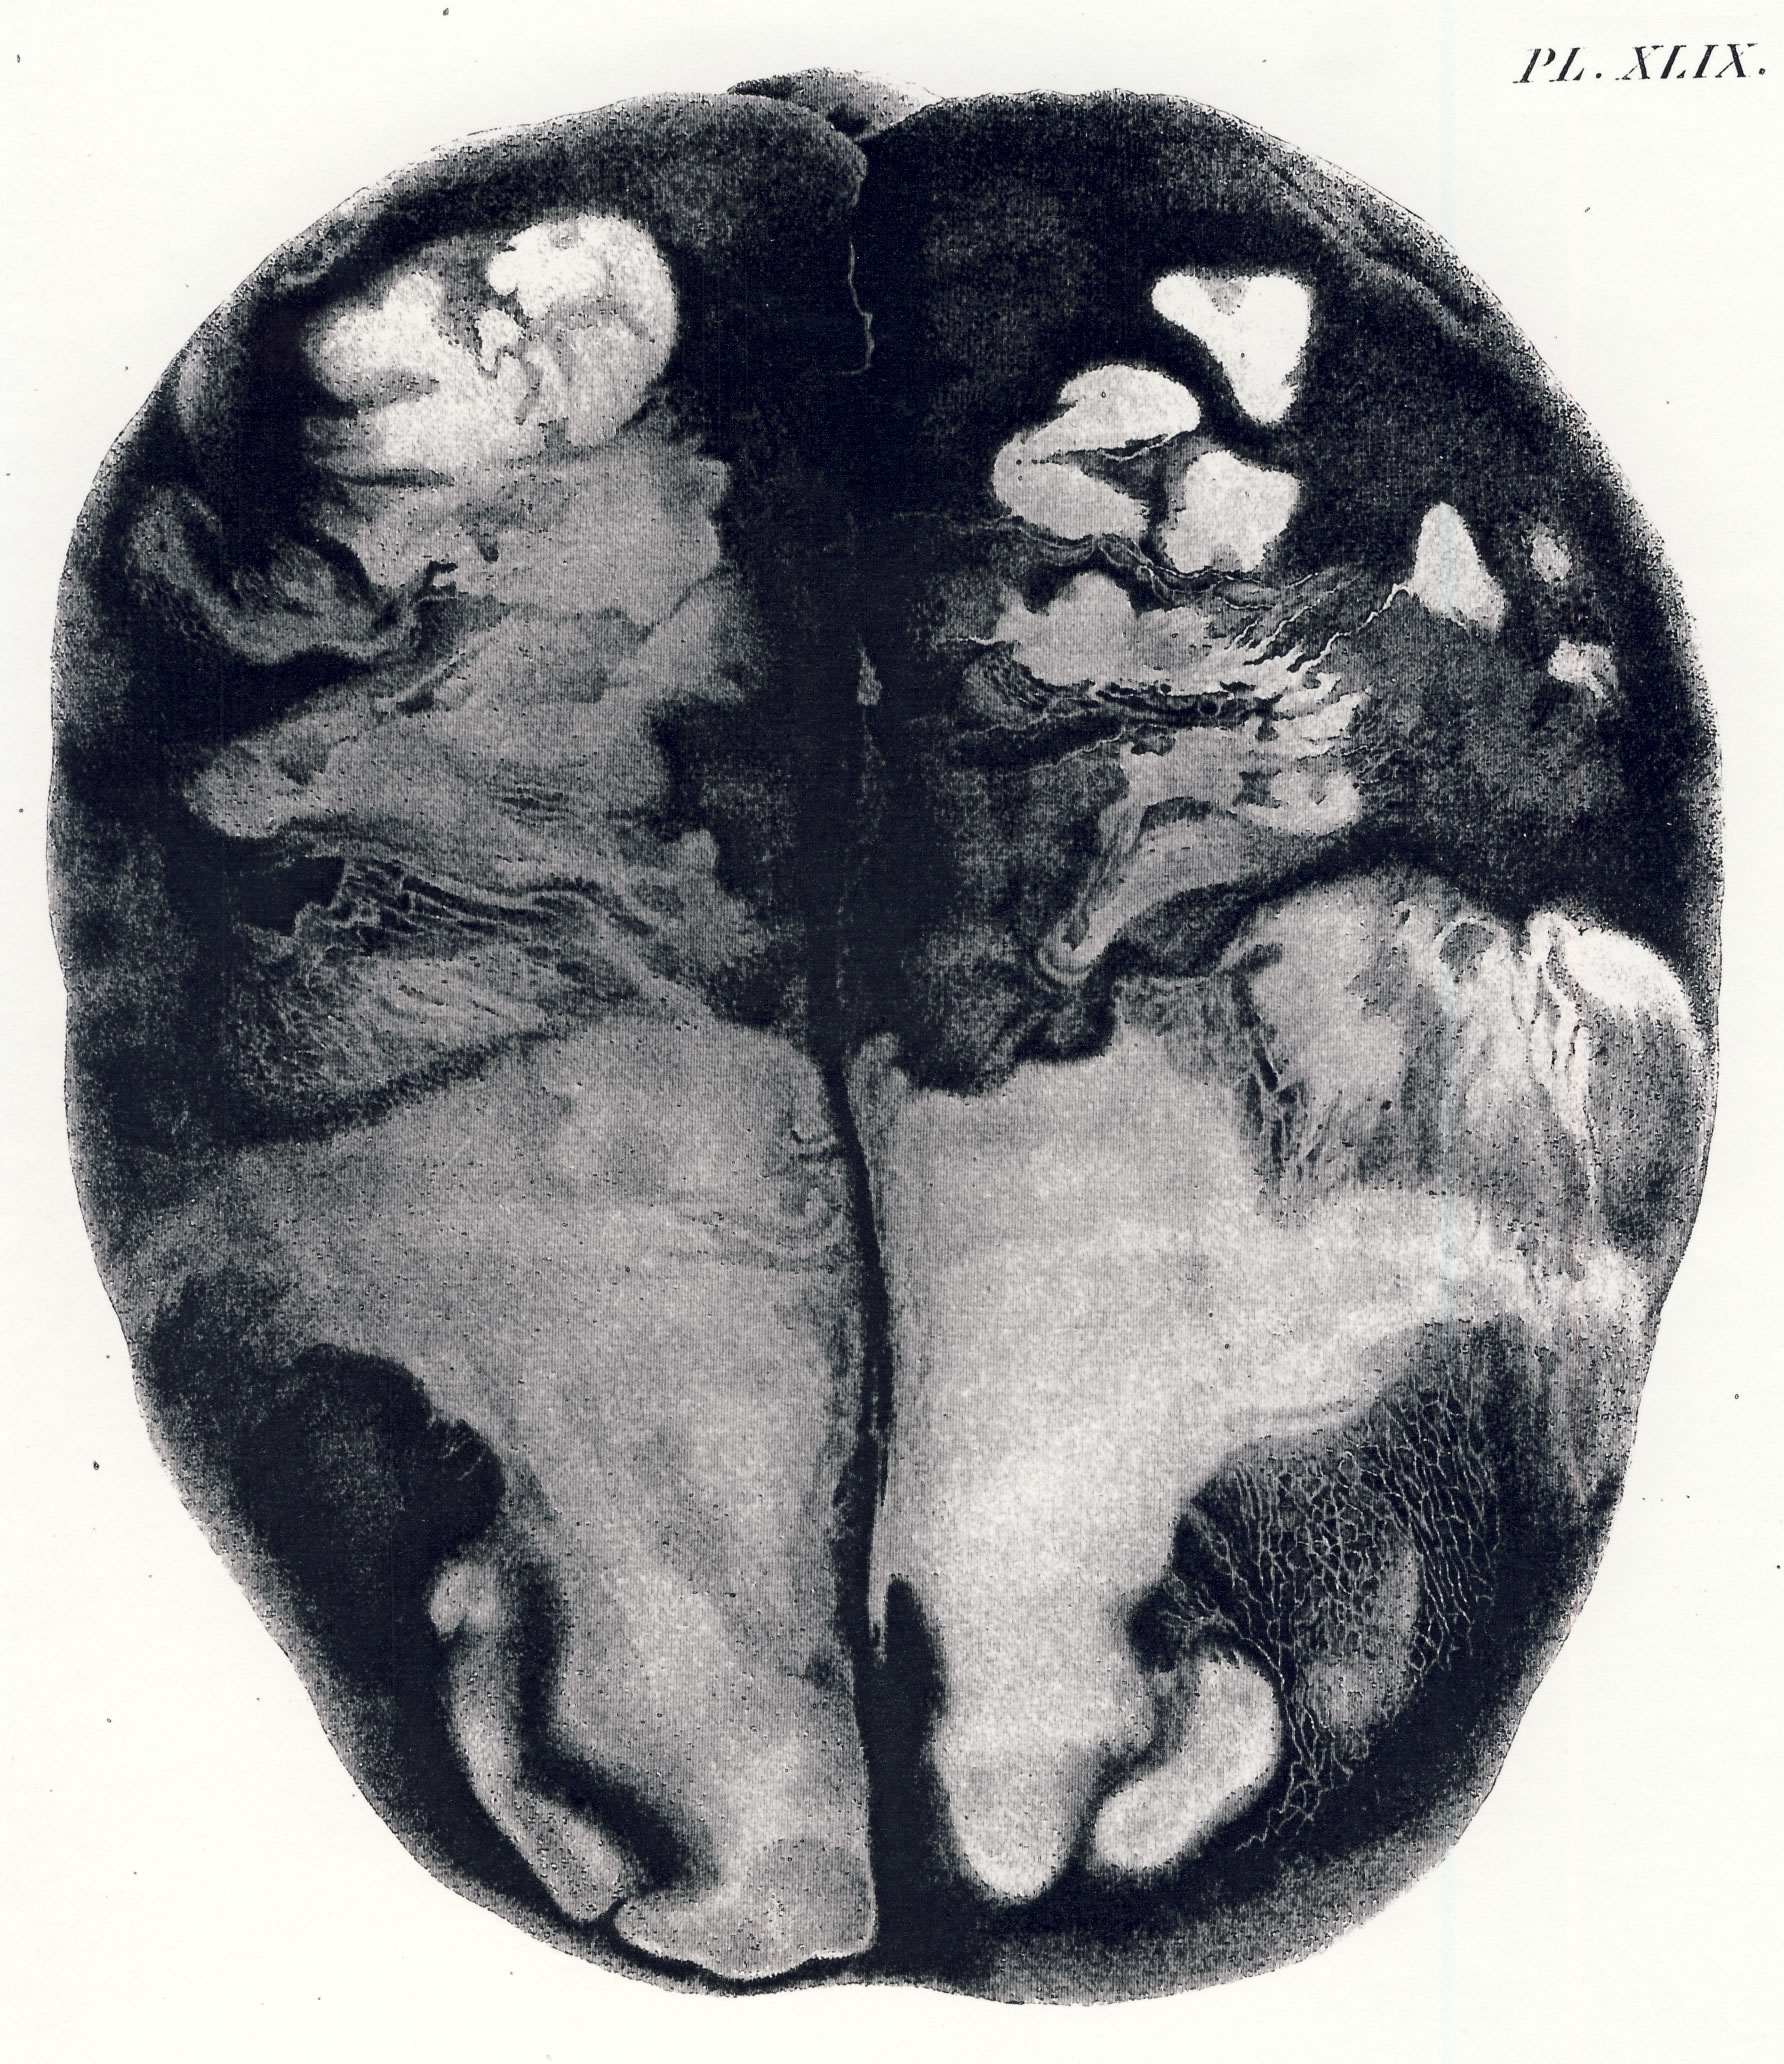

Gall, F. J. (1818). Anatomie et physiologie du système nerveux en général, et du cerveau en particulier, Avec des observations sur la possibilité de reconnoître plusieurs dispositions intellectuelles et morales de l´homme et des animaux, par la configuration de leurs têtes.

Librairie Grecque-Latine-Allemande, Vol. 3, I-XXXV u. 1-379 100 planches.